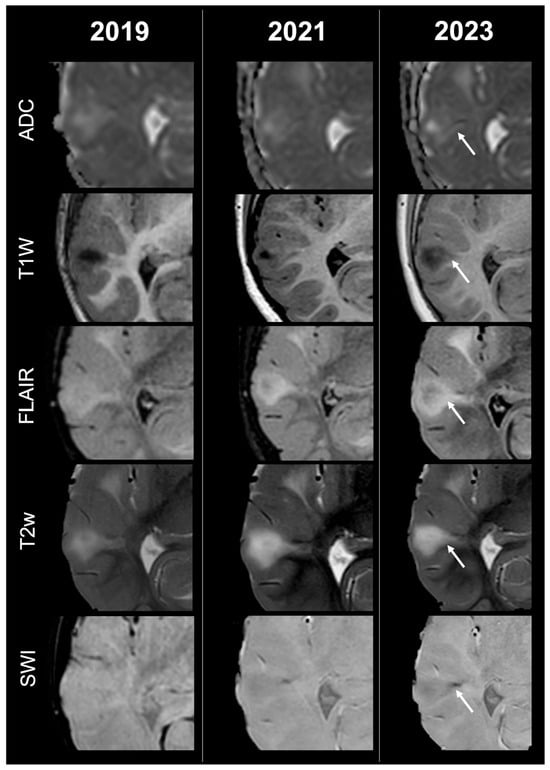

Cortical Tubers’ Transformation in Pediatric Patients Diagnosed with Tuberous Sclerosis Complex: A Retrospective Longitudinal MRI Analysis

Background: Cortical tubers (CTs) are hallmark brain lesions in tuberous sclerosis complex (TSC), historically considered stable in number over time; prior literature has correlated overall CT burden on magnetic resonance imaging (MRI) with disease severity. As longitudinal imaging studies assessing CTs’ evolution over time are lacking, we aim to investigate temporal changes in CTs—both in number and signal—on MRI in a cohort of pediatric TSC patients. Methods: A retrospective single-center analysis was conducted on 57 pediatric TSC patients who underwent longitudinal MRI studies in a 10-year span. Required MRI sequences included volumetric unenhanced T1-weighted, SWI, T2w and/or FLAIR. CTs were evaluated by two neuroradiologists and classified into five subtypes (A, B, C1, C2, D) according to signal characteristics. Statistical comparison was performed using t-tests. Results: Paired t-test analysis demonstrated a significant longitudinal increase in the overall number of CTs, rising from 16.11 ± 12.43 at baseline to 18.77 ± 13.29 at follow-up (mean difference = −2.67, 95% CI [−3.94, −1.39]; t (56) = 4.19; p < 0.0001), corresponding to a moderate effect size (Cohen’s d ≈ 0.56). When stratified by age, patients <2 years—representing the incompletely myelinated subgroup—showed a more pronounced increase in CT burden, from 19.46 ± 15.21 to 24.17 ± 15.75 (mean difference = −4.71, 95% CI [−7.37, −2.04]; t (23) = 3.65; p = 0.0013; d ≈ 0.75). In contrast, patients aged ≥2 years demonstrated a smaller but still significant increase, from 13.67 ± 9.45 to 14.85 ± 9.64 (mean difference = −1.18, 95% CI [−2.08, −0.28]; t (32) = 2.68; p = 0.0115; d ≈ 0.46). Direct comparison between the two subgroups using Welch’s two-sample t-test confirmed that the mean CT count in patients <2 years was significantly higher than in those ≥2 years (mean difference = 3.53 ± 1.36; t = 2.59; df = 28.4; p = 0.0075), with a large effect size (Cohen’s d ≈ 0.78). Type C1-C2 tubers evolved from pre-existing earlier-stage lesions, while most newly visible CTs over time were type A-B. Type D tubers remained rare and derived from earlier-stage CTs. Conclusions: Contrary to previous assumptions, CTs in pediatric TSC showed a tendency to increase in number and evolve in signal over time, thus challenging the notion of stability and suggesting dynamic behavior. Incomplete myelination in early infancy may impact MRI CTs detection by reducing contrast with surrounding brain tissue, potentially leading to their underestimation/misidentification. Full article

Show Figures

Figure 1